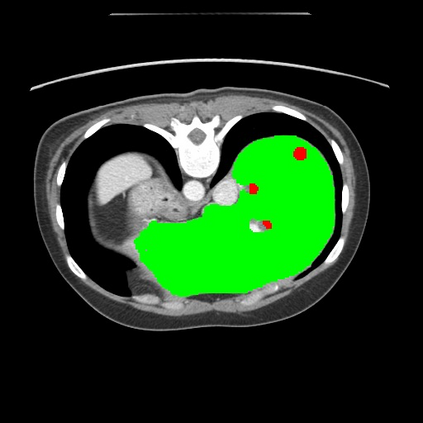

Transformers have made remarkable progress towards modeling long-range dependencies within the medical image analysis domain. However, current transformer-based models suffer from several disadvantages: (1) existing methods fail to capture the important features of the images due to the naive tokenization scheme; (2) the models suffer from information loss because they only consider single-scale feature representations; and (3) the segmentation label maps generated by the models are not accurate enough without considering rich semantic contexts and anatomical textures. In this work, we present CASTformer, a novel type of generative adversarial transformers, for 2D medical image segmentation. First, we take advantage of the pyramid structure to construct multi-scale representations and handle multi-scale variations. We then design a novel class-aware transformer module to better learn the discriminative regions of objects with semantic structures. Lastly, we utilize an adversarial training strategy that boosts segmentation accuracy and correspondingly allows a transformer-based discriminator to capture high-level semantically correlated contents and low-level anatomical features. Our experiments demonstrate that CASTformer dramatically outperforms previous state-of-the-art transformer-based approaches on three benchmarks, obtaining 2.54%-5.88% absolute improvements in Dice over previous models. Further qualitative experiments provide a more detailed picture of the model's inner workings, shed light on the challenges in improved transparency, and demonstrate that transfer learning can greatly improve performance and reduce the size of medical image datasets in training, making CASTformer a strong starting point for downstream medical image analysis tasks.